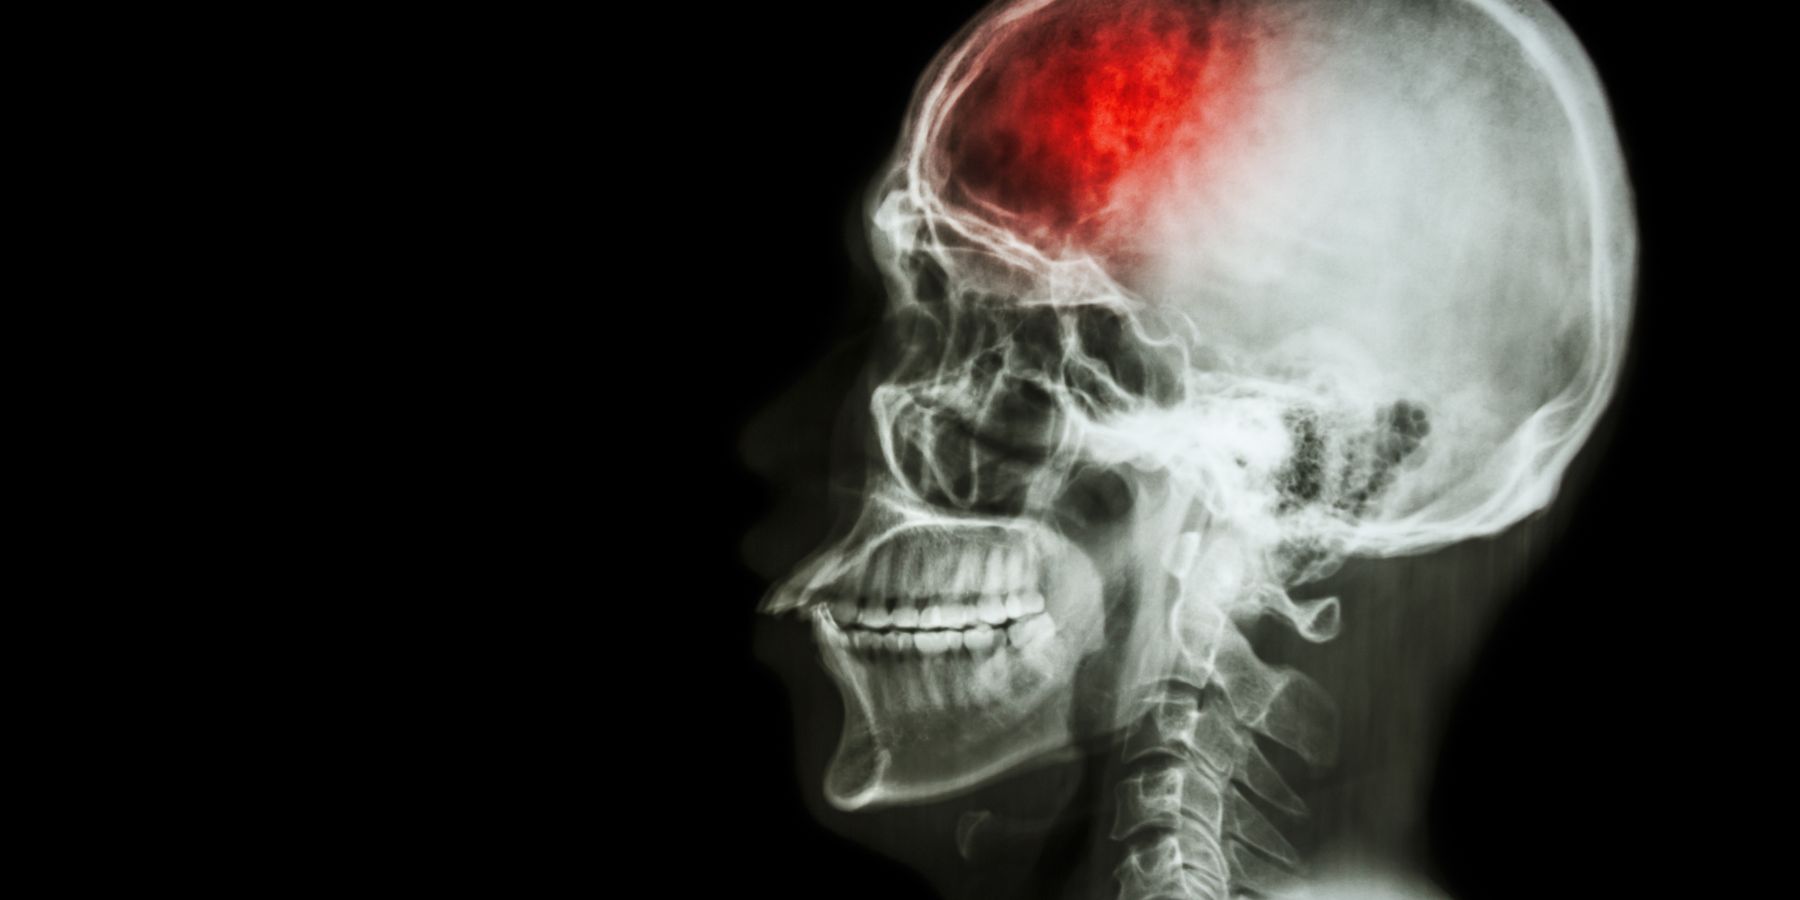

Reconocer los Primeros Síntomas de un ACV y la Importancia de la Rehabilitación Temprana diciembre 9, 2025 No hay comentarios Saber más »

Guía Completa sobre la Rehabilitación después de un ACV diciembre 3, 2025 No hay comentarios Saber más »